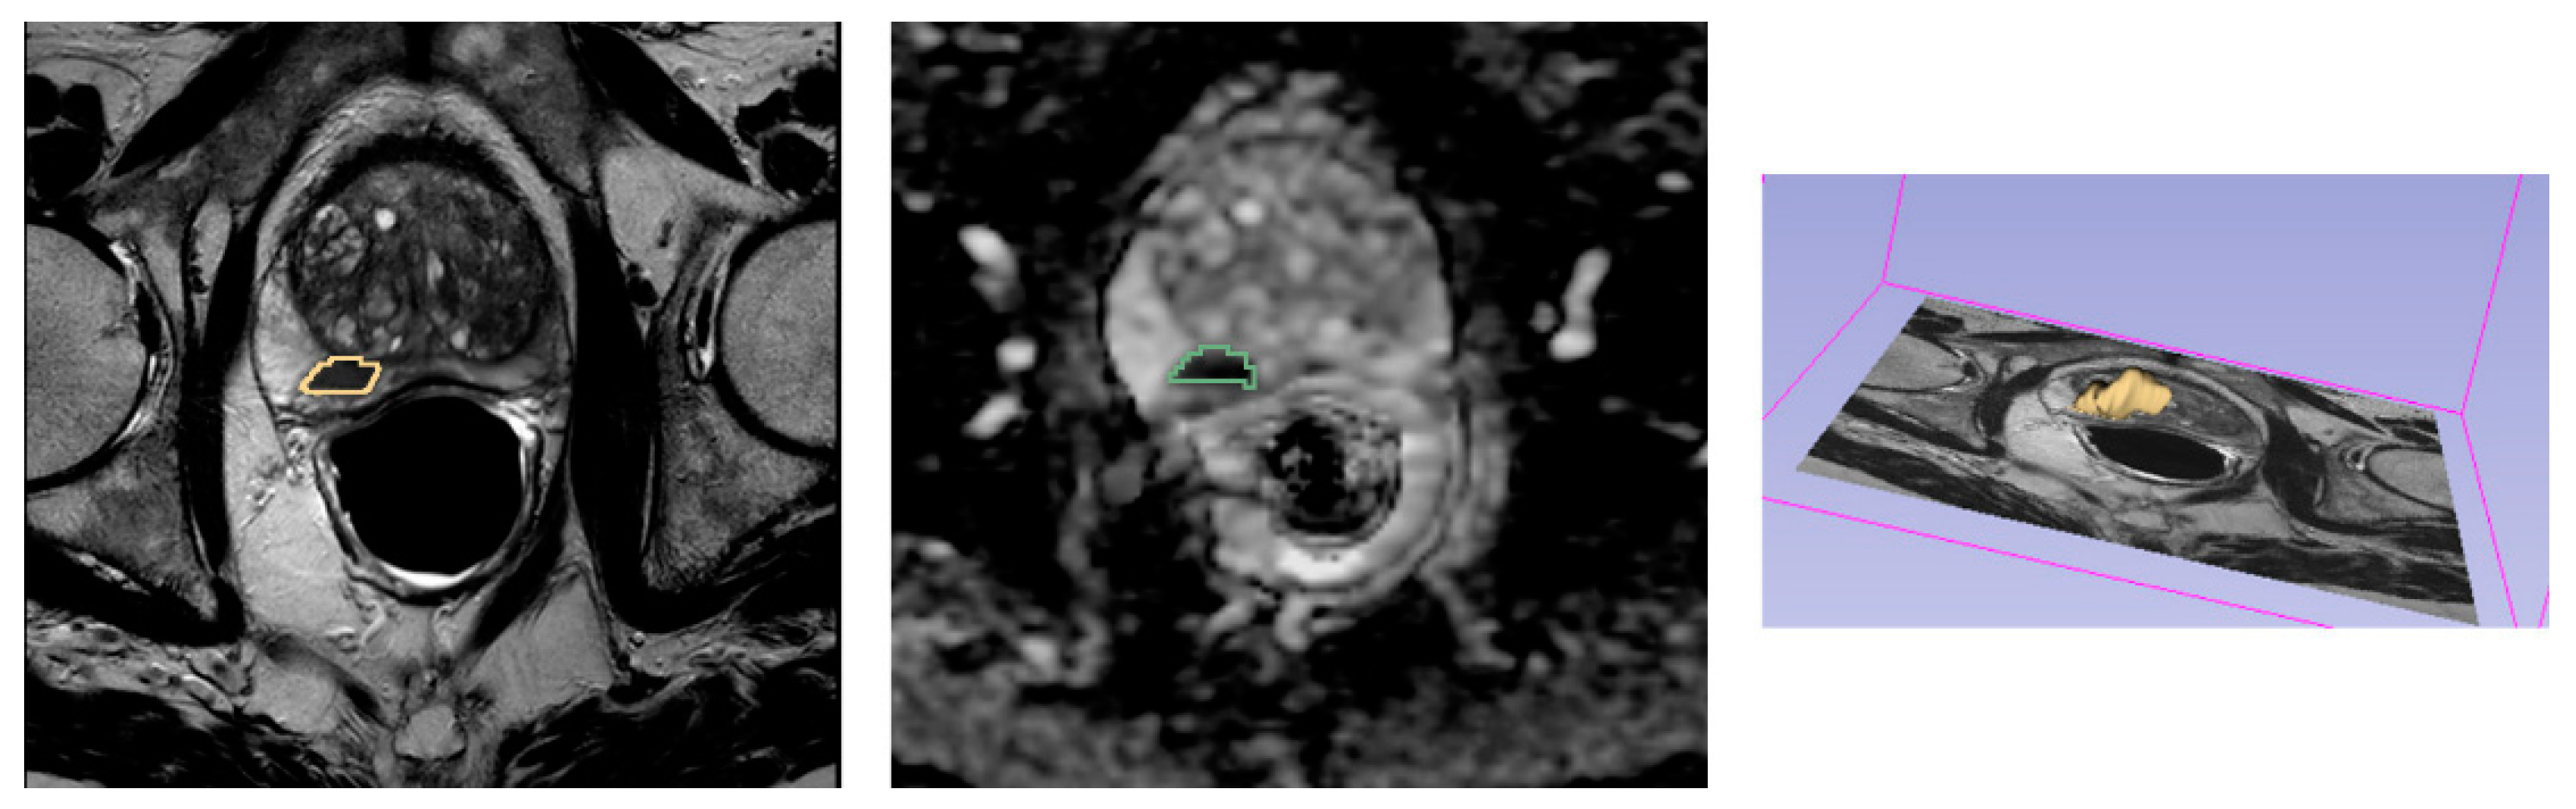

2.4.1. MRI Images Post-Processing

2.4.2. Tumor Volume Segmentation